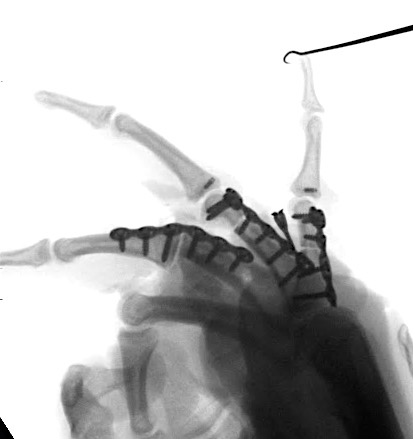

Case 2:

A 20-year-old male suffered a complex multi-digit injury of the right hand requiring revascularization and stabilization of both proximal phalanx and PIP joint fractures (Figs 5 - 8). Multiple plates, including the rotation correction plate from the 1.5 module of the VA Locking Hand System were used for fixation. The Variable Angle Locking system is ideal when only two screws, either proximal or distal, are able to be inserted due to space limitation.

One major advantage of variable angle technology in very distal phalangeal fractures is the ability to be extremely flexible with a wide range of fixation options. Freedom of implant placement assists early mobilization, vital in these complex fractures with associated soft-tissue trauma.